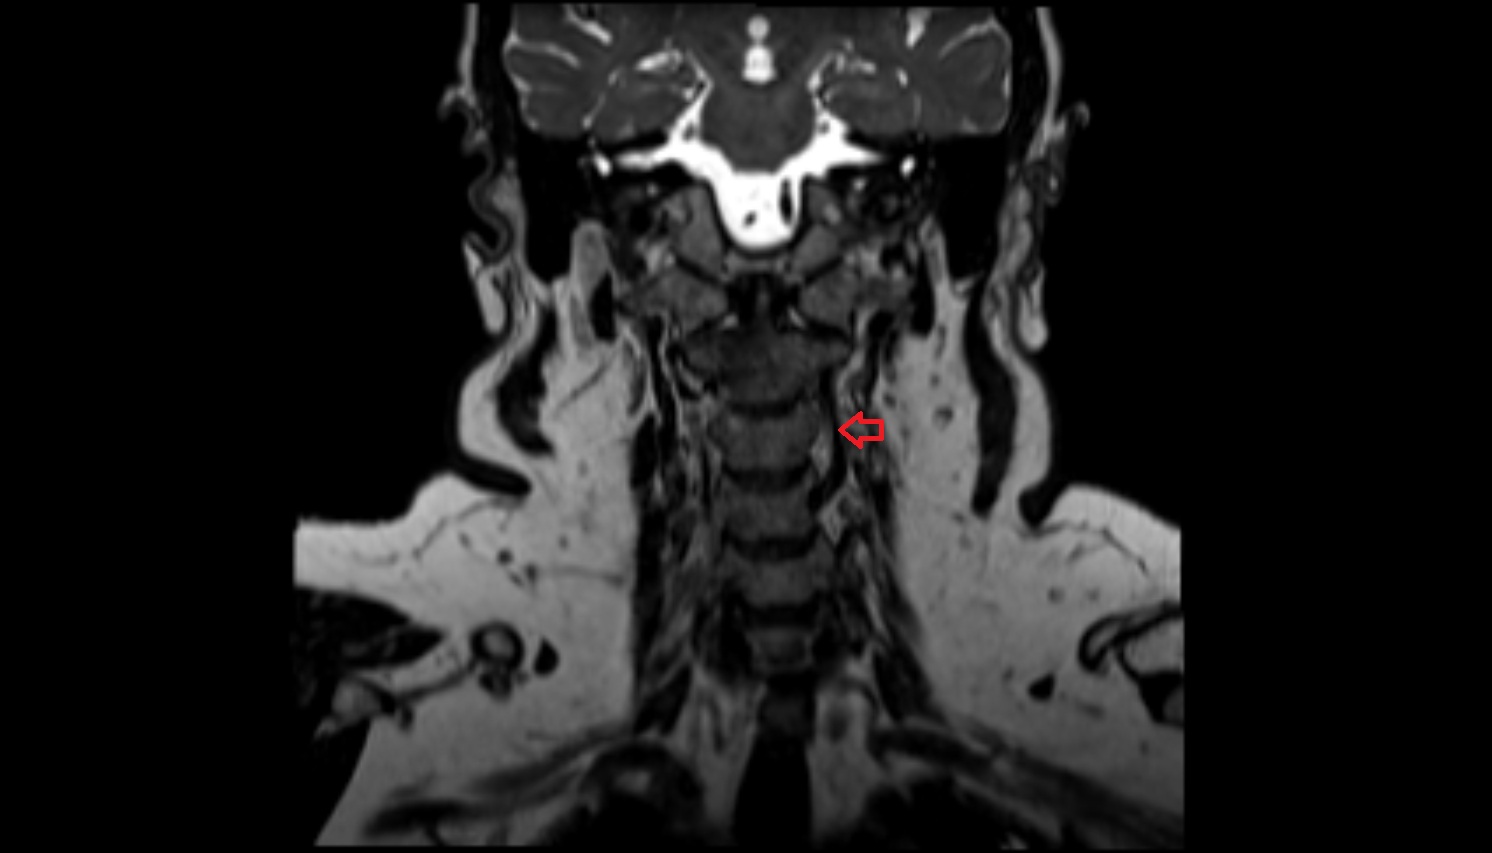

- Upper cervical spinal cord

- Spinal cord

- subarachnoid space of spinal cord